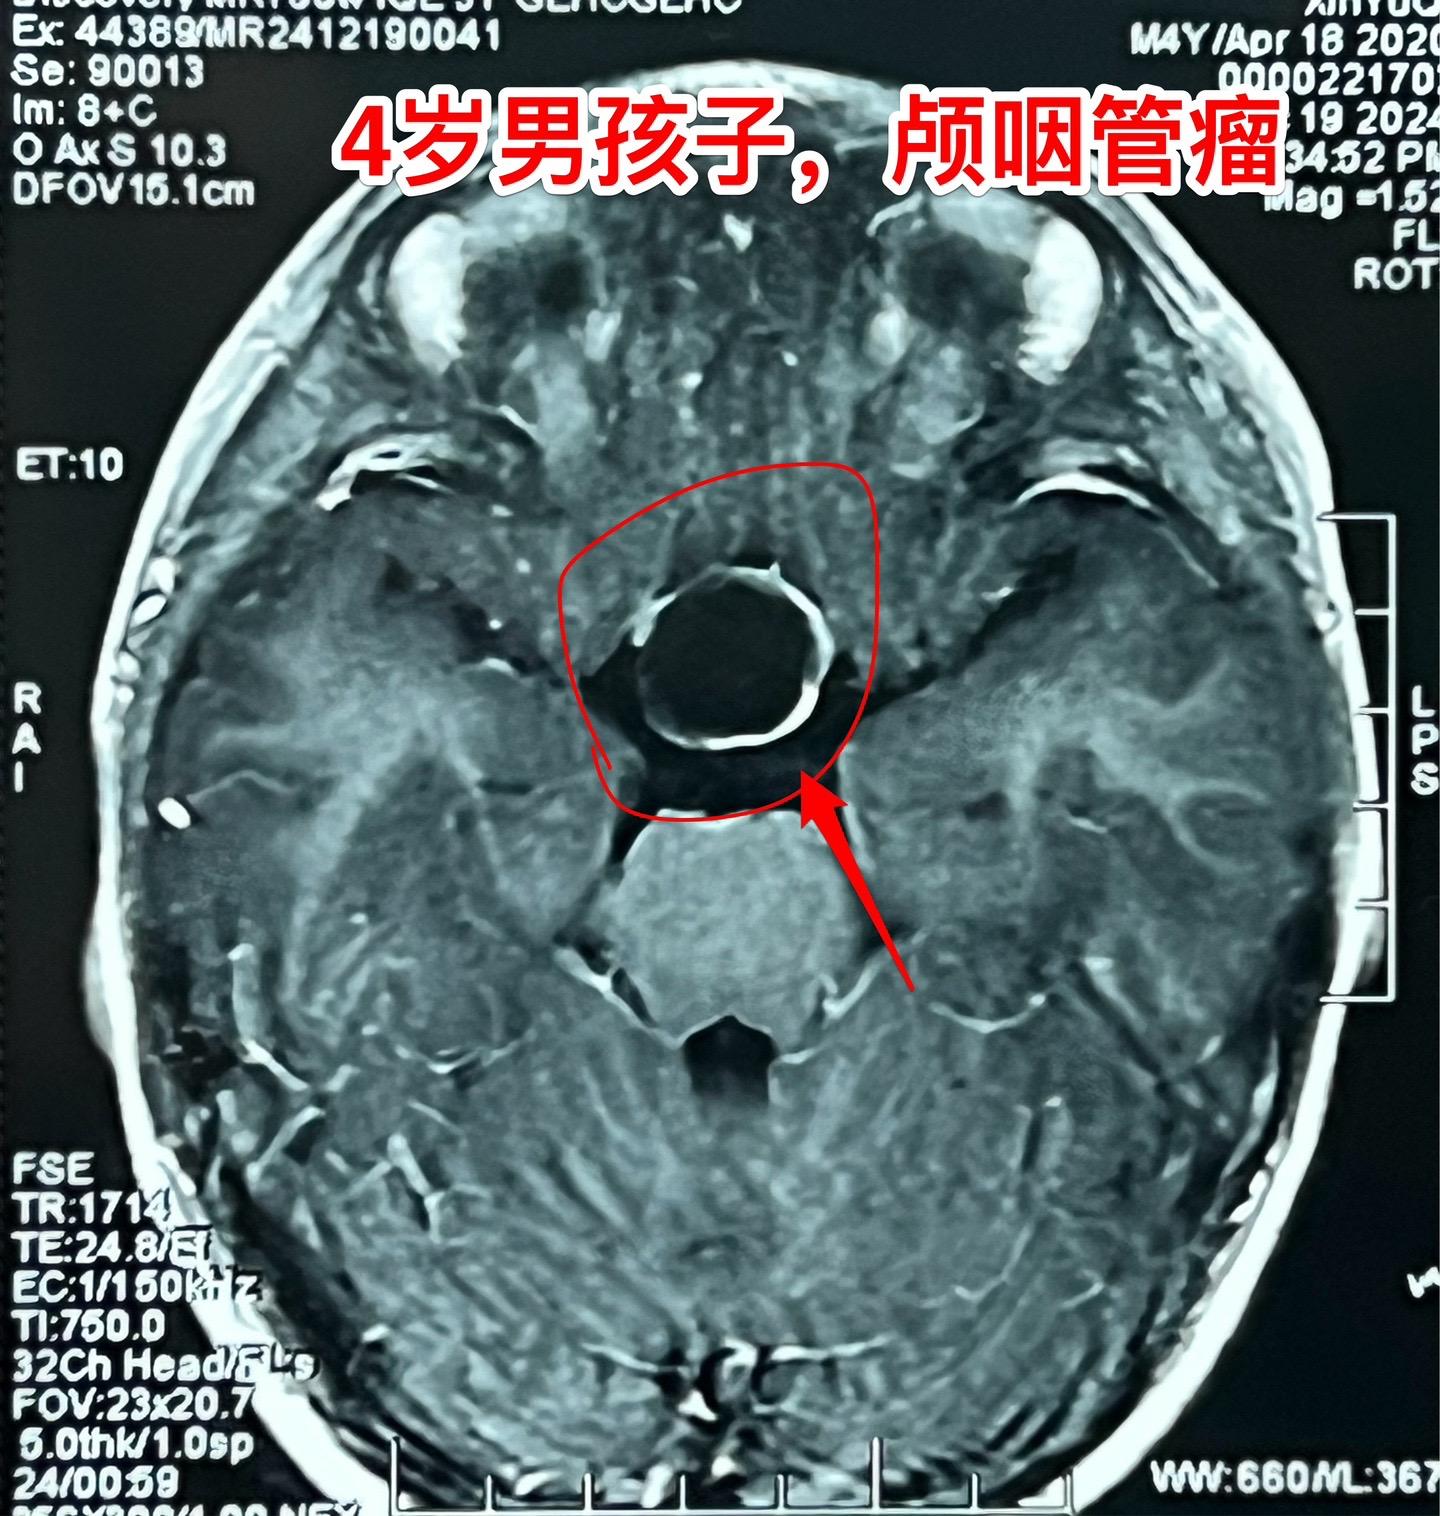

12月26日两个颅咽管瘤手术。第一个四岁男孩子,因为头部受伤,作CT发现颅咽管瘤。家长没有犹豫,选择尽快作手术。手术中将颅咽管瘤完全切除,垂体柄和垂体保留约50%。早作手术的好处就是肿瘤与周围结构粘连不紧密,易于分离,有助于完全切除肿瘤。 第二个病人是14岁男孩子,颅咽管瘤手术后6年,术后半年就发现了肿瘤复发,随后观察,多次复查磁共振显示肿瘤在长大。这个瘤也是在垂体窝内,和第一个病人一样,但是肿瘤与周围结构粘连紧密,切除的难度更大,也得到了完全切除。